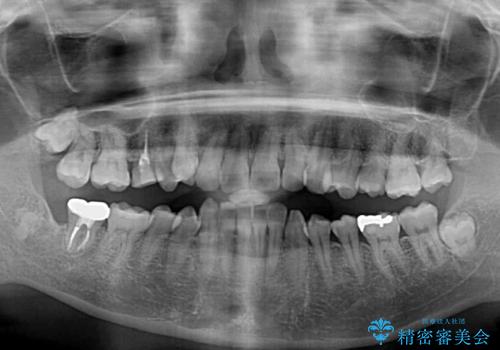

上顎小臼歯を抜歯するかどうか悩みましたが、八重歯の後方に失活歯があること、治療前に上顎正中が概ね人中に合っていることから、右上第二小臼歯を抜歯することとしました。

片側での抜歯であると、正中が抜歯した方向にずれていくため、左上の奥歯を遠心移動させる目的でアンカースクリューと補助装置を併用した上で、ワイヤー装置にて矯正治療を行うこととしました。